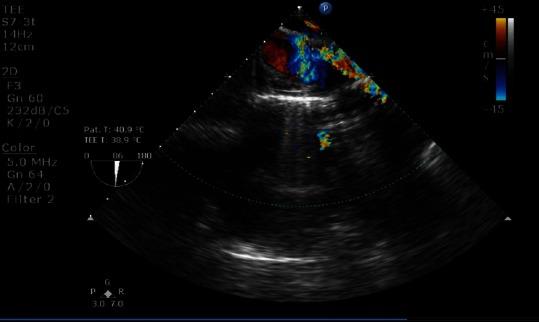

Aortopulmonary window (APW) is a relatively rare cardiac lesion representing approximately 0.2%-0.4% of all cardiac malformation. It is a cardiac abnormality that results from abnormal communication between the proximal aorta and the main pulmonary artery in the presence of two normally separated aortic and pulmonary valves. In the past, the diagnostic and surgical approach to APW was almost always preceded by cardiac catheterization. With recent advances in noninvasive approach and techniques of two-dimensional echocardiography diagnosis of the defect and associated anomalies are facilitated without a cath study. We report a 4-month-old infant with a distal APW who was referred to our center for surgical repair. We emphasize the usage of transesophageal echocardiography as a valuable intraoperative tool which not only confirms the preoperative diagnosis but also helps in assessing the surgical repair of an APW.

主肺动脉窗(APW)是一种相对罕见的心脏病变,约占所有心脏畸形的0.2%-0.4%。它是一种心脏异常,在主动脉瓣和肺动脉瓣正常分隔的情况下,由近端主动脉与主肺动脉之间的异常交通引起。过去,APW的诊断和手术方法几乎总是先进行心导管检查。随着无创方法和二维超声心动图技术的最新进展,无需心导管检查即可促进对该缺损及相关异常的诊断。我们报告一例4个月大患有远端APW的婴儿,转诊至我们中心进行手术修复。我们强调经食管超声心动图作为一种有价值的术中工具的应用,它不仅能确认术前诊断,还有助于评估APW的手术修复情况。